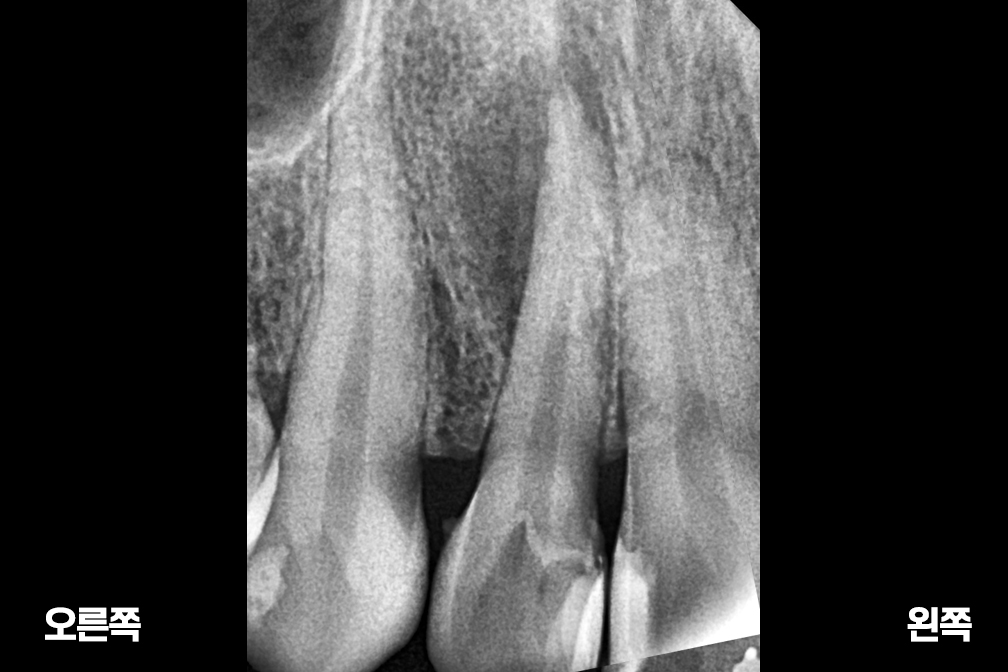

신경치료 윗 앞니 신경치료

신경치료

Before 2025년 9월 8일

After 2026년 1월 21일